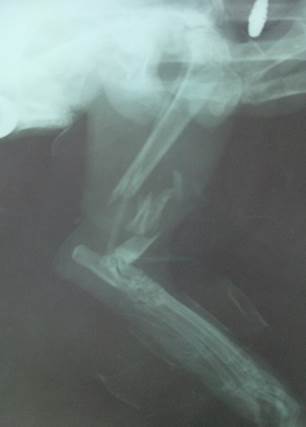

El diagnóstico se realizó mediante la combinación de anamnesis, examen físico ortopédico y, como técnica imagenológica, una radiografía con vista latero-lateral de la extremidad. El Rx evidenció una fractura múltiple (conminuta) de la porción distal de tibia derecha. En la Figura2 se aprecia una radiopacidad en el tejido blando que rodea la tibia que indica el edema inflamatorio, el hematoma y el compromiso grave de estos.

Fig. 2.

Fractura conminuta de la región distal de la tibia derecha. /Comminuted fracture of the distal region of the right tibia.